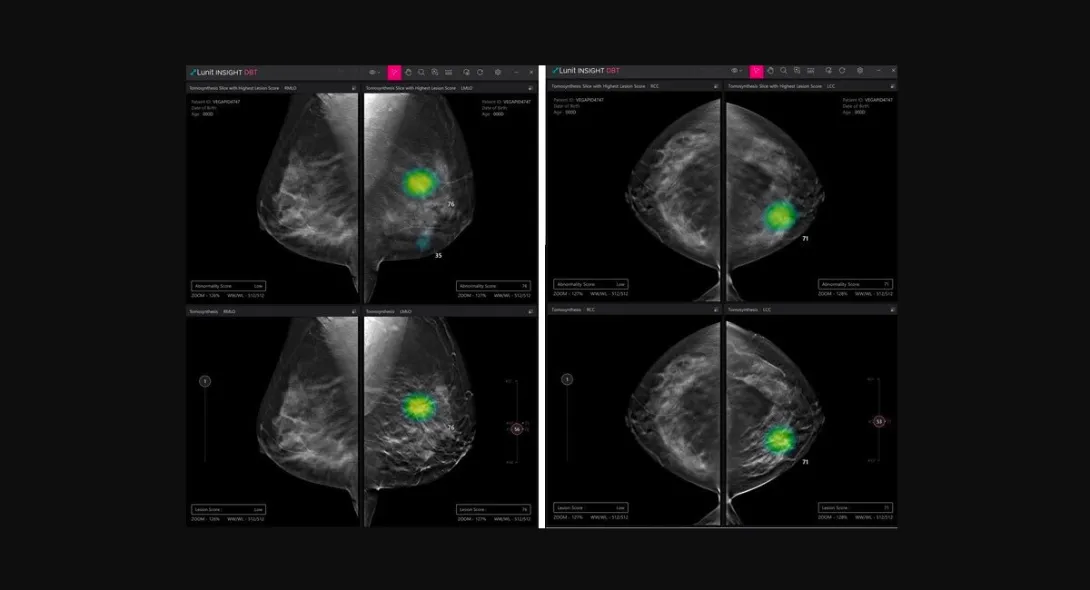

The company will introduce Lunit INSIGHT DBT which handpicks a 3D slice image with suspicious lesions among multiple images to accelerate reading and the Lunit INSIGHT Chest CT that automatically generates a detected module's location, type, volume and axial diameter.

"CT and DBT are more sophisticated examinations where you can further evaluate the specification of nodules or distinguish cancer. At this stage, our AI will be able to assist radiologists to diagnose cancer faster at higher accuracy," said Lunit Chief Product Officer Sunggyun Park.